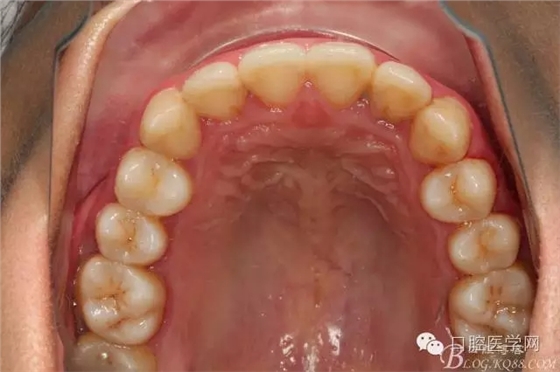

患者都是以刷牙出血為主訴。術(shù)前照片